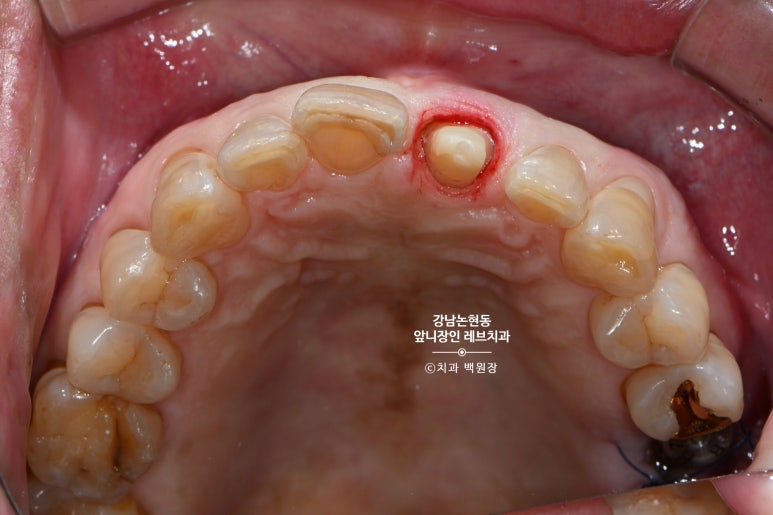

그런데 말입니다? 교합면에서 보면 꽤나 치아가 많이 남아보인단 말이지요.

입천장쪽 면에는 꽤나 치아가 남아있는것을 보실 수 있습니다.

그래서... 살려보자고 마음 먹어봤습니다.

씹는 면에서 보면 꽤나 깊이 치아의 경계가 형성된 것도 확인할 수 있으실겁니다.